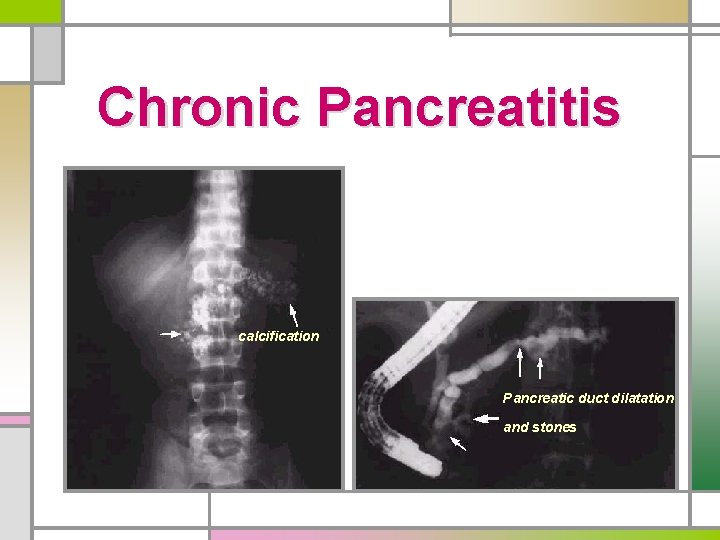

Chronic Pancreatitis calcification Pancreatic duct dilatation and stones